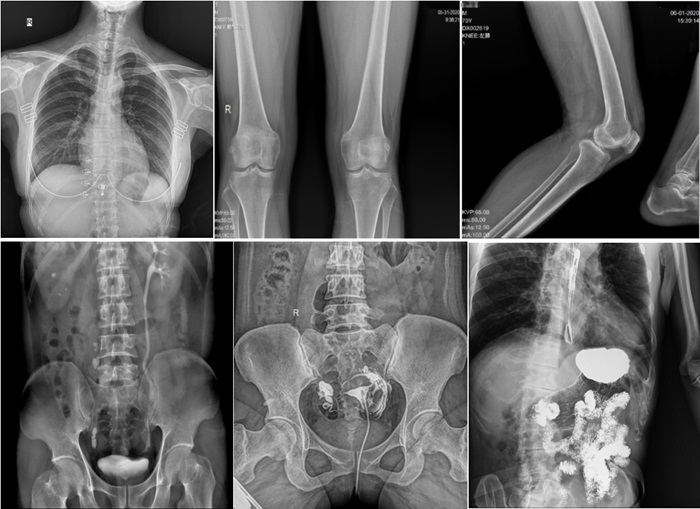

普利德動態平板DRF作為普放領域最新技術的代表,融合了攝影、透視和造影等多功能于一體,并能在可視化條件下進行高清點片,有效減少了傳統靜態DR盲拍造成漏診和誤診的風險。其17×17英寸大幅面成像,能夠通過一次曝光實現胸部、腹部全覆蓋。設備支持最高30幀/秒的采集幀率,確保了動態影像的流暢性,便于醫生觀察細微病變,提升診斷精準性。

在實際應用中,普利德動態平板DRF展現出了多種優勢。例如,在胸部影像檢查中,它清晰顯示肺部紋理和結節,為肺癌早期篩查提供有力支持;在骨科領域,可用于骨折的診斷和復位效果評估,幫助醫生制定更精準的治療方案;在消化系統檢查中,能有效發現胃腸道疾病的異常。

在婦科方面,不僅能夠直觀的觀察子宮形態、大小,輸卵管各部有無扭曲、管腔粘連以及梗塞情況,還可以在加壓推注下,使部分輸卵管輕、中度堵塞的患者得以通暢,起到有效的治療作用。